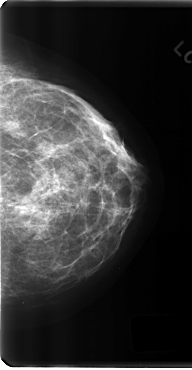

C_0197_1.LEFT_CC

LEFT_CC LINES 4808 PIXELS_PER_LINE 2496 BITS_PER_PIXEL 12 RESOLUTION 50 NON_OVERLAY